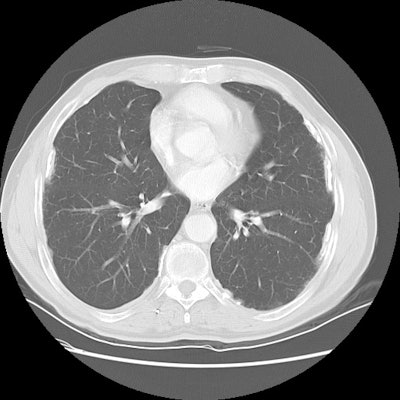

The case below demonstrates extensive pleural plaque disease in a patient with a history of asbestos exposure:

(Click CXR to enlarge)